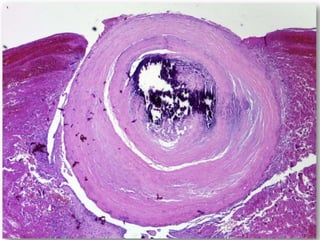

Uma mulher de 72 anos apresentou um nódulo assintomático na mucosa labial inferior há cerca de três meses. Após biópsia, o diagnóstico foi de flebólito, descartando as hipóteses iniciais de miofibroma ou neurofibroma.